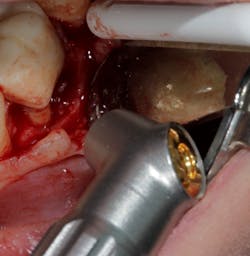

Technology solution: Many dental lasers can focus their beam smaller than 1 mm to enter the furcation for detoxification.8 For example, a 9.3-micron CO2 laser has a spot size of the focal laser beam in the control range of .25 mm–1.25 mm so the beam can be directed into the furcation entrance, which allows previously difficult furcal defects to be detoxified prior to regenerative therapy. Because of this enhanced ability to detoxify, this laser has been able to change the prognosis of once hopeless teeth (figure 3) and allow for tissue regeneration instead of extraction.